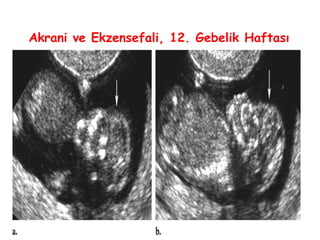

Akrani ve Ekzensefali, 12. Gebelik Haftası

Akrani, Exensefali, Anensefali

• Anensefali en sık görülen santral sinir sistemi

anomalisidir, nöral tübün baş kısmının yetersiz

kapanması sonucu oluşur.

• Akraninin bir sonucu olan eksensefalide ilk

trimesterde etkilenen beyin tipik olarak normalden

çeşitli derecelerde distorsiyona doğru ilerler ve

ilerleyen haftalarda genellikle anensefali görüntüsü

ortaya çıkar

• Bu bulgulara dikkat edilirse gebeliğin 12-14.

haftalarında anensefali tanısı rahatlıkla konulabilir.

• Kalvaryum ve serebral hemisferlerin yokluğu,

gebeliğin 2. ya da 3. trimesterinde anensefali

tanısının esasını teşkil etmektedir.